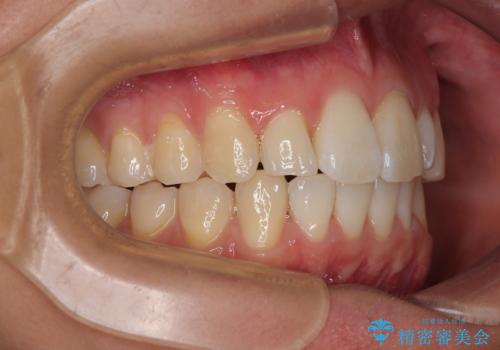

前歯のデコボコをインビザラインで綺麗に改善

- 上下前歯のデコボコとクロスバイトを気にして来院された患者様です。

インビザラインを用い、IPR(歯と歯の間を削る)と歯列全体を拡大させることで、歯並びを整えていくこととしました。

毎日22時間の装着時間を徹底してくださったのですが、左右ともに臼歯が咬合しなくなるという、インビザライン独特の症状が強く長く続いてしまい、終了するまでに長期間を要してしまいました。